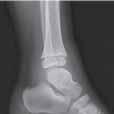

Podział złamań kości rosnących, tzw. złamań nasadowych: A – schematyczne przedstawienie klasyfikacji złamań; B – SH I (RTG, widok z przodu i z boku); C – SH II (RTG, widok z przodu i z boku); D – SH II (TK, widok z boku); E – SH III (RTG, widok z przodu i z boku); F – SH IV (RTG, widok z przodu i z boku); G – SH V (RTG, widok z przodu i z boku).

Rozpoznanie

Objawy złamania to silny ból uniemożliwiający stanie i chodzenie, zniekształcenie obrysów stawu kolanowego przez krwiak i różnego stopnia przemieszczenie nasady kości piszczelowej. Należy dokładnie zbadać stan ukrwienia i unaczynienia kończyny pod kątem objawów uszkodzenia tętnicy podkolanowej i nerwu strzałkowego. Trzeba ocenić bolesność uciskową oraz napięcie w przedziałach powięziowych podudzia: przednim, bocznym, tylnym powierzchownym i tylnym głębokim. U pacjentów z podejrzeniem wzmożonego ciśnienia wewnątrzprzedziałowego należy wielokrotnie powtarzać badanie ukrwienia i unerwienia kończyny, a w razie zaistnienia wskazań wykonać bezpośredni pomiar ciśnienia w przedziałach. Powinno się zawsze podejrzewać możliwość uszkodzeń więzadłowych współistniejących ze złamaniem. Badania obrazowe to RTG w pozycji AP, bocznej i skośnej. Wykonanie badania TK może być konieczne w celu pełnej oceny rozległości

złamania. W przypadku podejrzenia uszkodzenia tętnicy podkolanowej należy wykonać angio-TK lub arteriografię.

Leczenie złamania bliższej nasady piszczeli w przypadku uszkodzenia typu 1 i 2 według Saltera i Harrisa leczymy nieoperacyjnie. Należy wykonać zamkniętą repozycję i unieruchomić w opatrunku gipsowym udowym w zgięciu kolana 30–60°, zapewniającym najlepszą stabilność odłamów. Okres unieruchomienia wynosi od 6 do 7 tygodni. Po tym czasie usuwamy gips i zaczynamy ćwiczenia zwiększające zakres ruchomości stawu kolanowego oraz wzmacniające siłę mięśnia czworogłowego. Ważne jest, by prowadzić częste kontrole stanu ukrwienia i unaczynienia oraz kontrole radiologiczne w celu wykrycia ewentualnych przemieszczeń odłamów. Złamania pierwotnie niestabilne lub wtórnie przemieszczone wymagają zamkniętej repozycji stabilizacji drutami K. Typ 3 i 4

Złamania rzepki i podudzia

złamania według Saltera i Harrisa wymaga leczenia operacyjnego w postaci otwartej repozycji i stabilizacji śrubami. Należy unikać krzyżowania metalu zespalającego z chrząstką wzrostową. Kończynę zgiętą w kolanie do 30° unieruchamia się w gipsie udowym na okres 6–8 tygodni. Po tym czasie rozpoczynamy ćwiczenia czynne poprawiające zakres ruchomości kończyny.